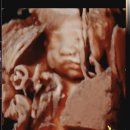

• (주)토탈그린 | 고양시 연세 맘스그린 26주 입체초음파 가격 비용 실패 후 성공 후기

초음파까지 토탈 비용은 20,300원이다. ​ ​ - 맘스그린 주차 - ​ 맘스그린의 유일한 단점은 주차이다. 건물주차가 안되기 때문에 근처 공영주차장에 하는데, 날이...병원에서 지정된 주차장은 없고 1,200원 지원이 된다. ​ ​ ​ 26주차 4일 맘스그린 방문 후기 ​ ​ 간호사님과 원장님이 너무 친절해서 진료받는 내내 심신이 편안...

낭만수박(2025-12-19 08:00:00)